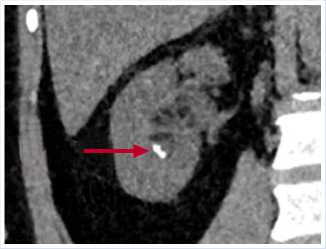

Рис. 5. МСКТ в нативном режиме, сделанная в июне 2023 г. Стрелкой указан конкремент нижней трети левого мочеточника, мигрировавший из области ЛМС.

слева, размерами до 4,8 x 3,5 мм, плотностью до +452 HU–при исследовании выявлен в нижней трети левого мочеточника. Левый мочеточник не расширен (Рис. 3–5).